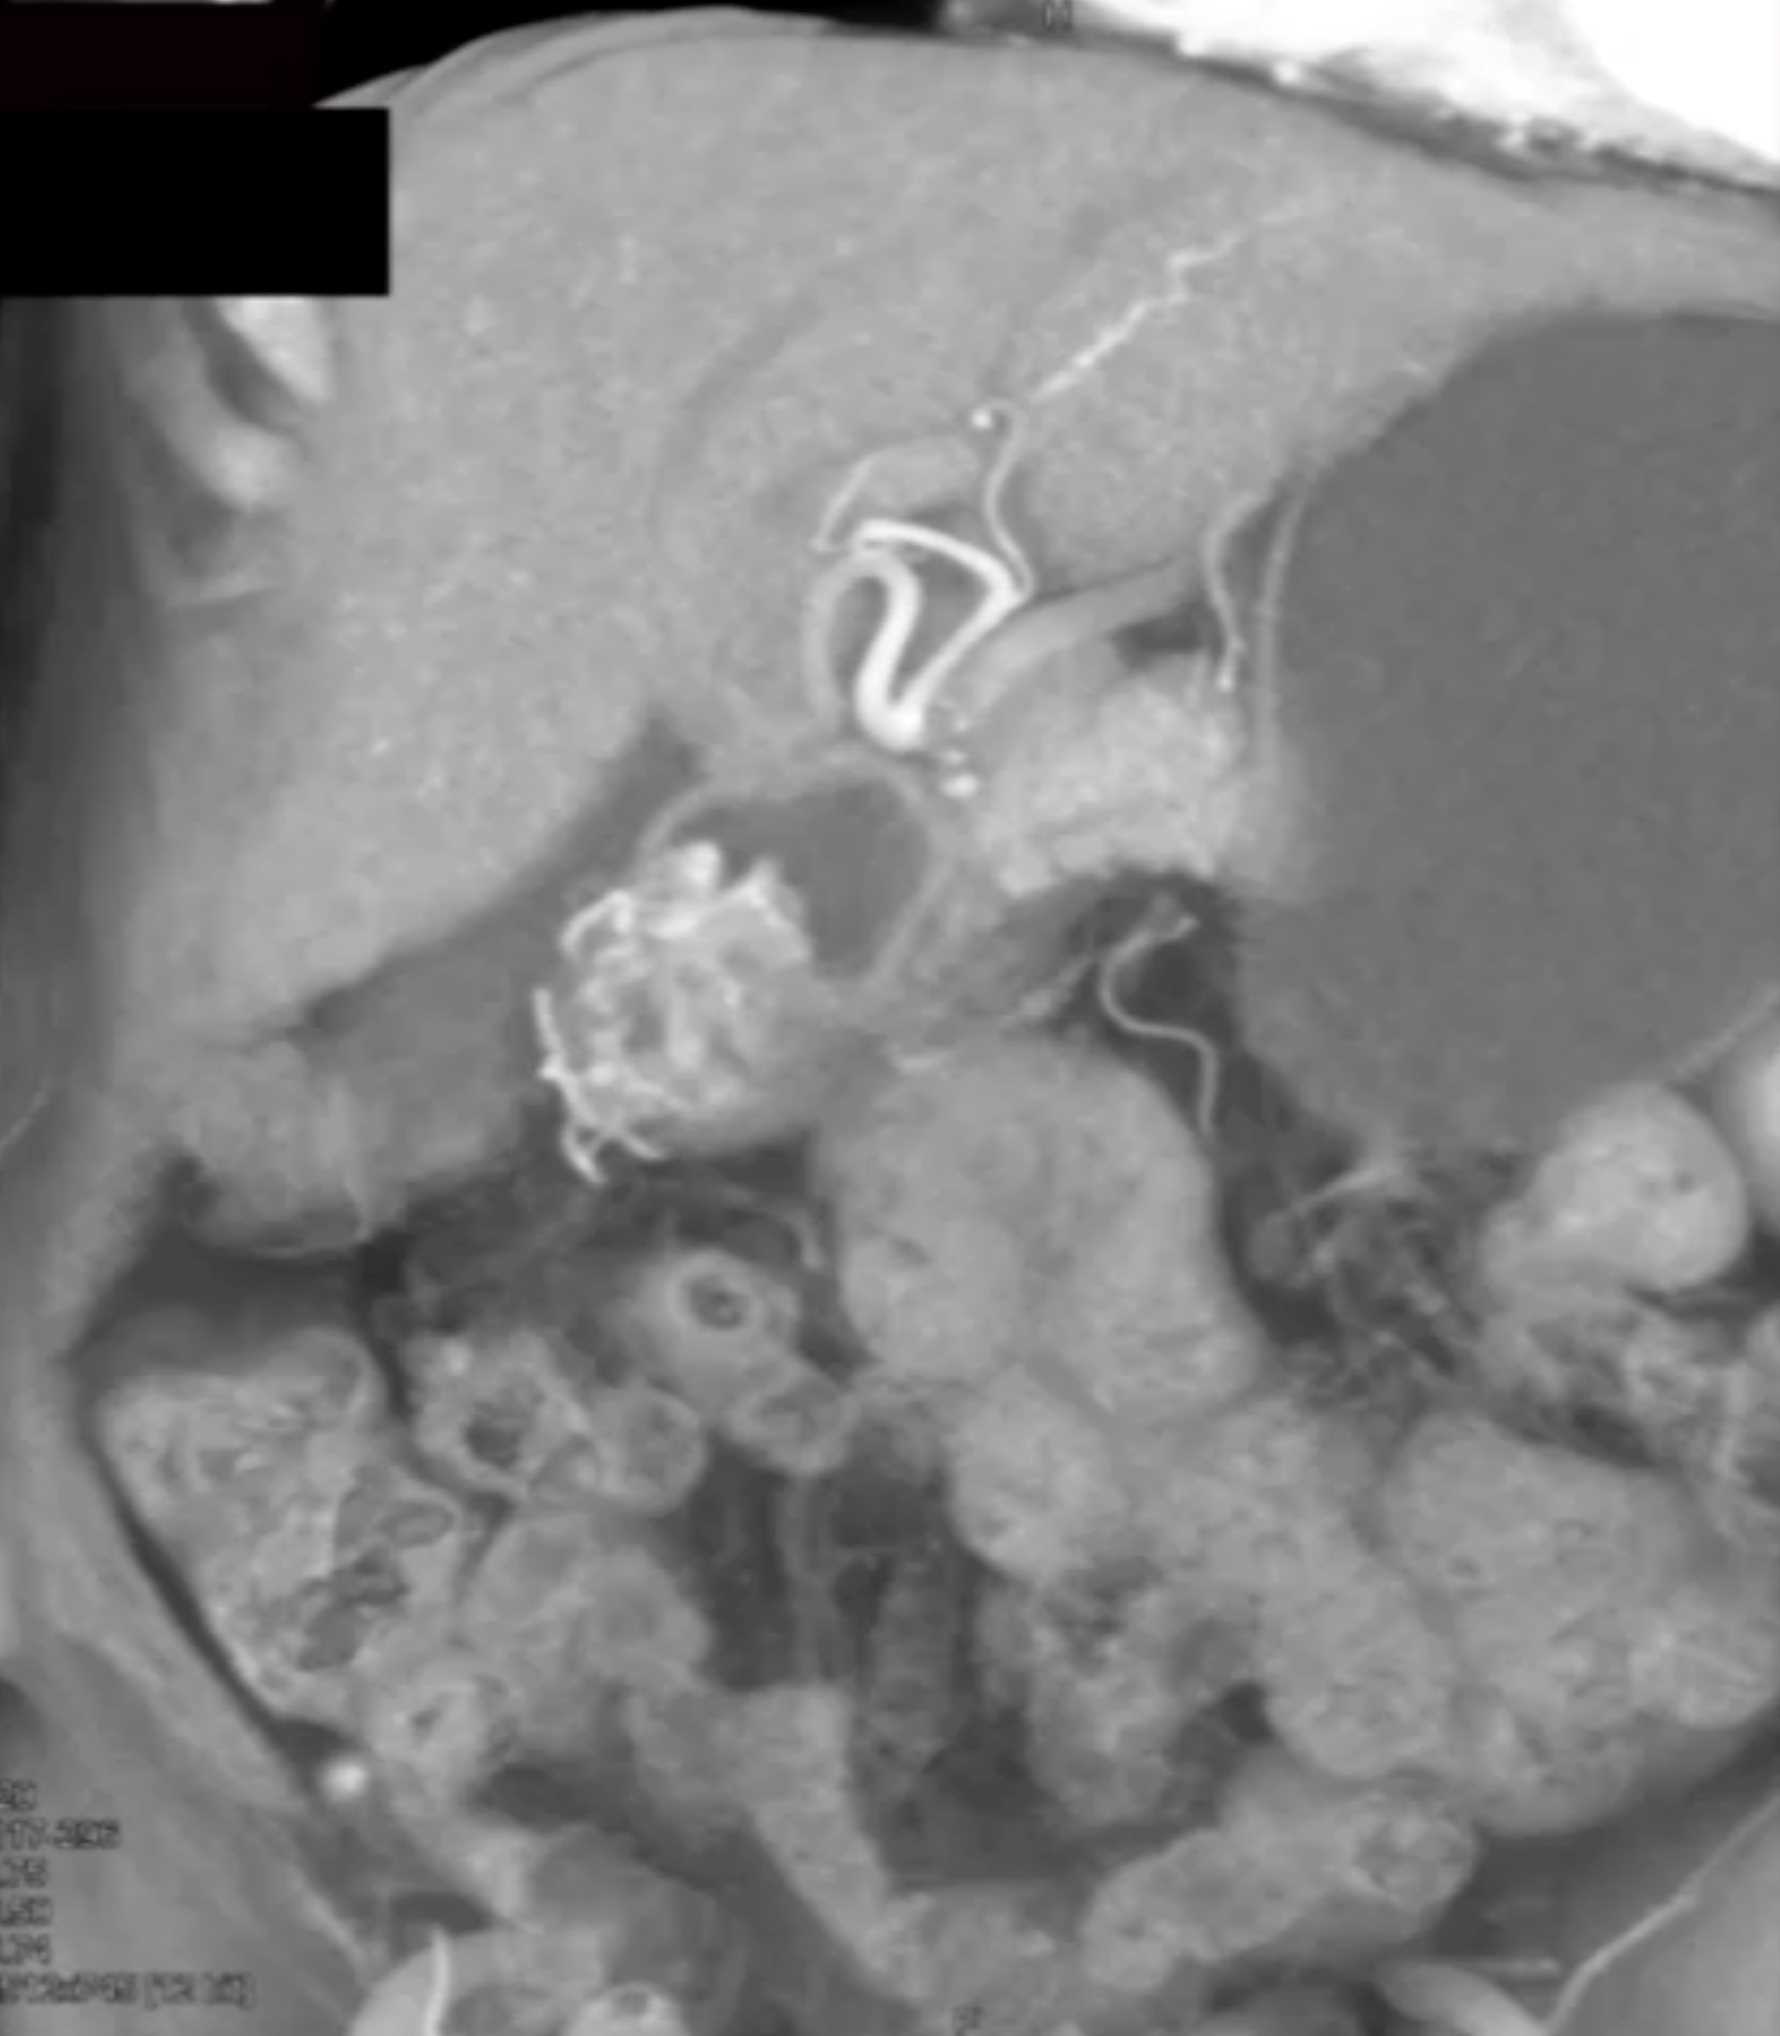

Watermelon Stomach (Gastric Antral Vascular Ectasis)